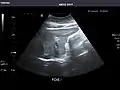

Pancreas

Pancreas: Visualized portions unremarkable.